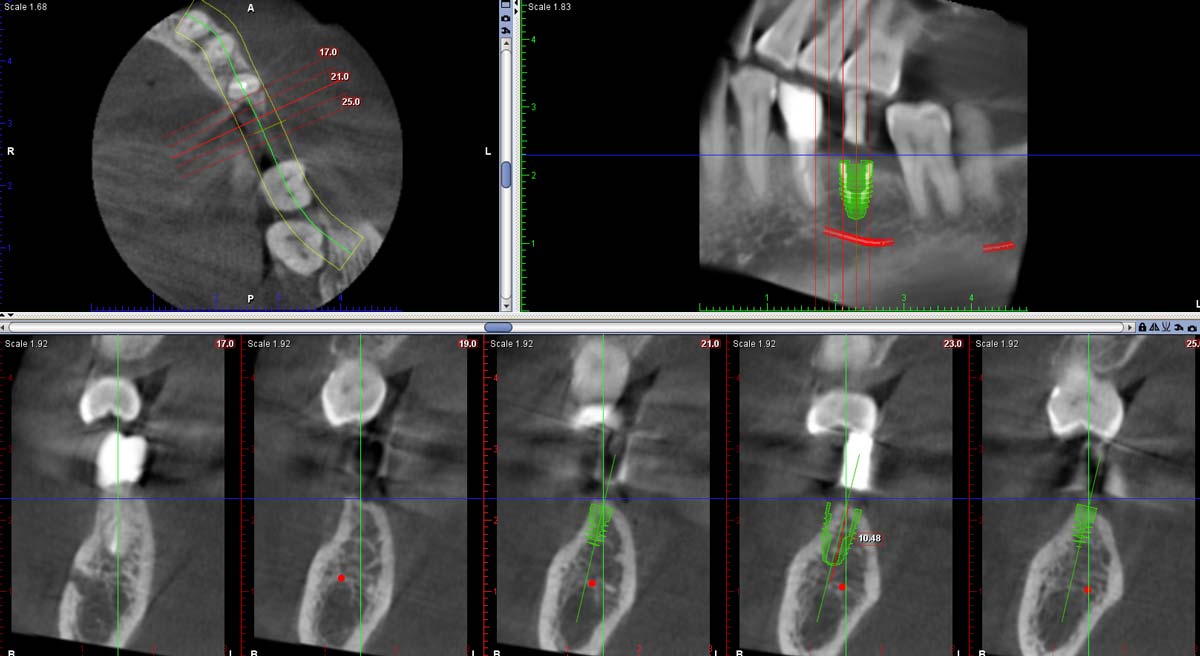

首先我們須先看斷層掃描中,假想牙齒下方植體出落的位置周圍是否有合理的骨頭包圍?在下顎,植體長度受限於下顎齒槽神經管的位置,那麼植牙跟隨咬合角度放入後,是否有理想或合理的長度寬度就很值得先思考。

像如下的case植牙長度只能放到8 mm,再多就可能撞到神經管,這時候植體寬度就很重要,以第一大臼齒最好有5.5mm以上較安全,以迎接在咬合功能行使上的力量。那麼換算骨寬度,為加上植體的頰舌側左右需有2 mm,理想在牙脊寬度一共需9.5 mm以上,等同於現況植入後有大半是露出來的,為保守起見,我們常常先補一次骨粉和再生膜,另外在再生膜下方搭一德國帳棚釘,以維持住新骨頭生長的空間。